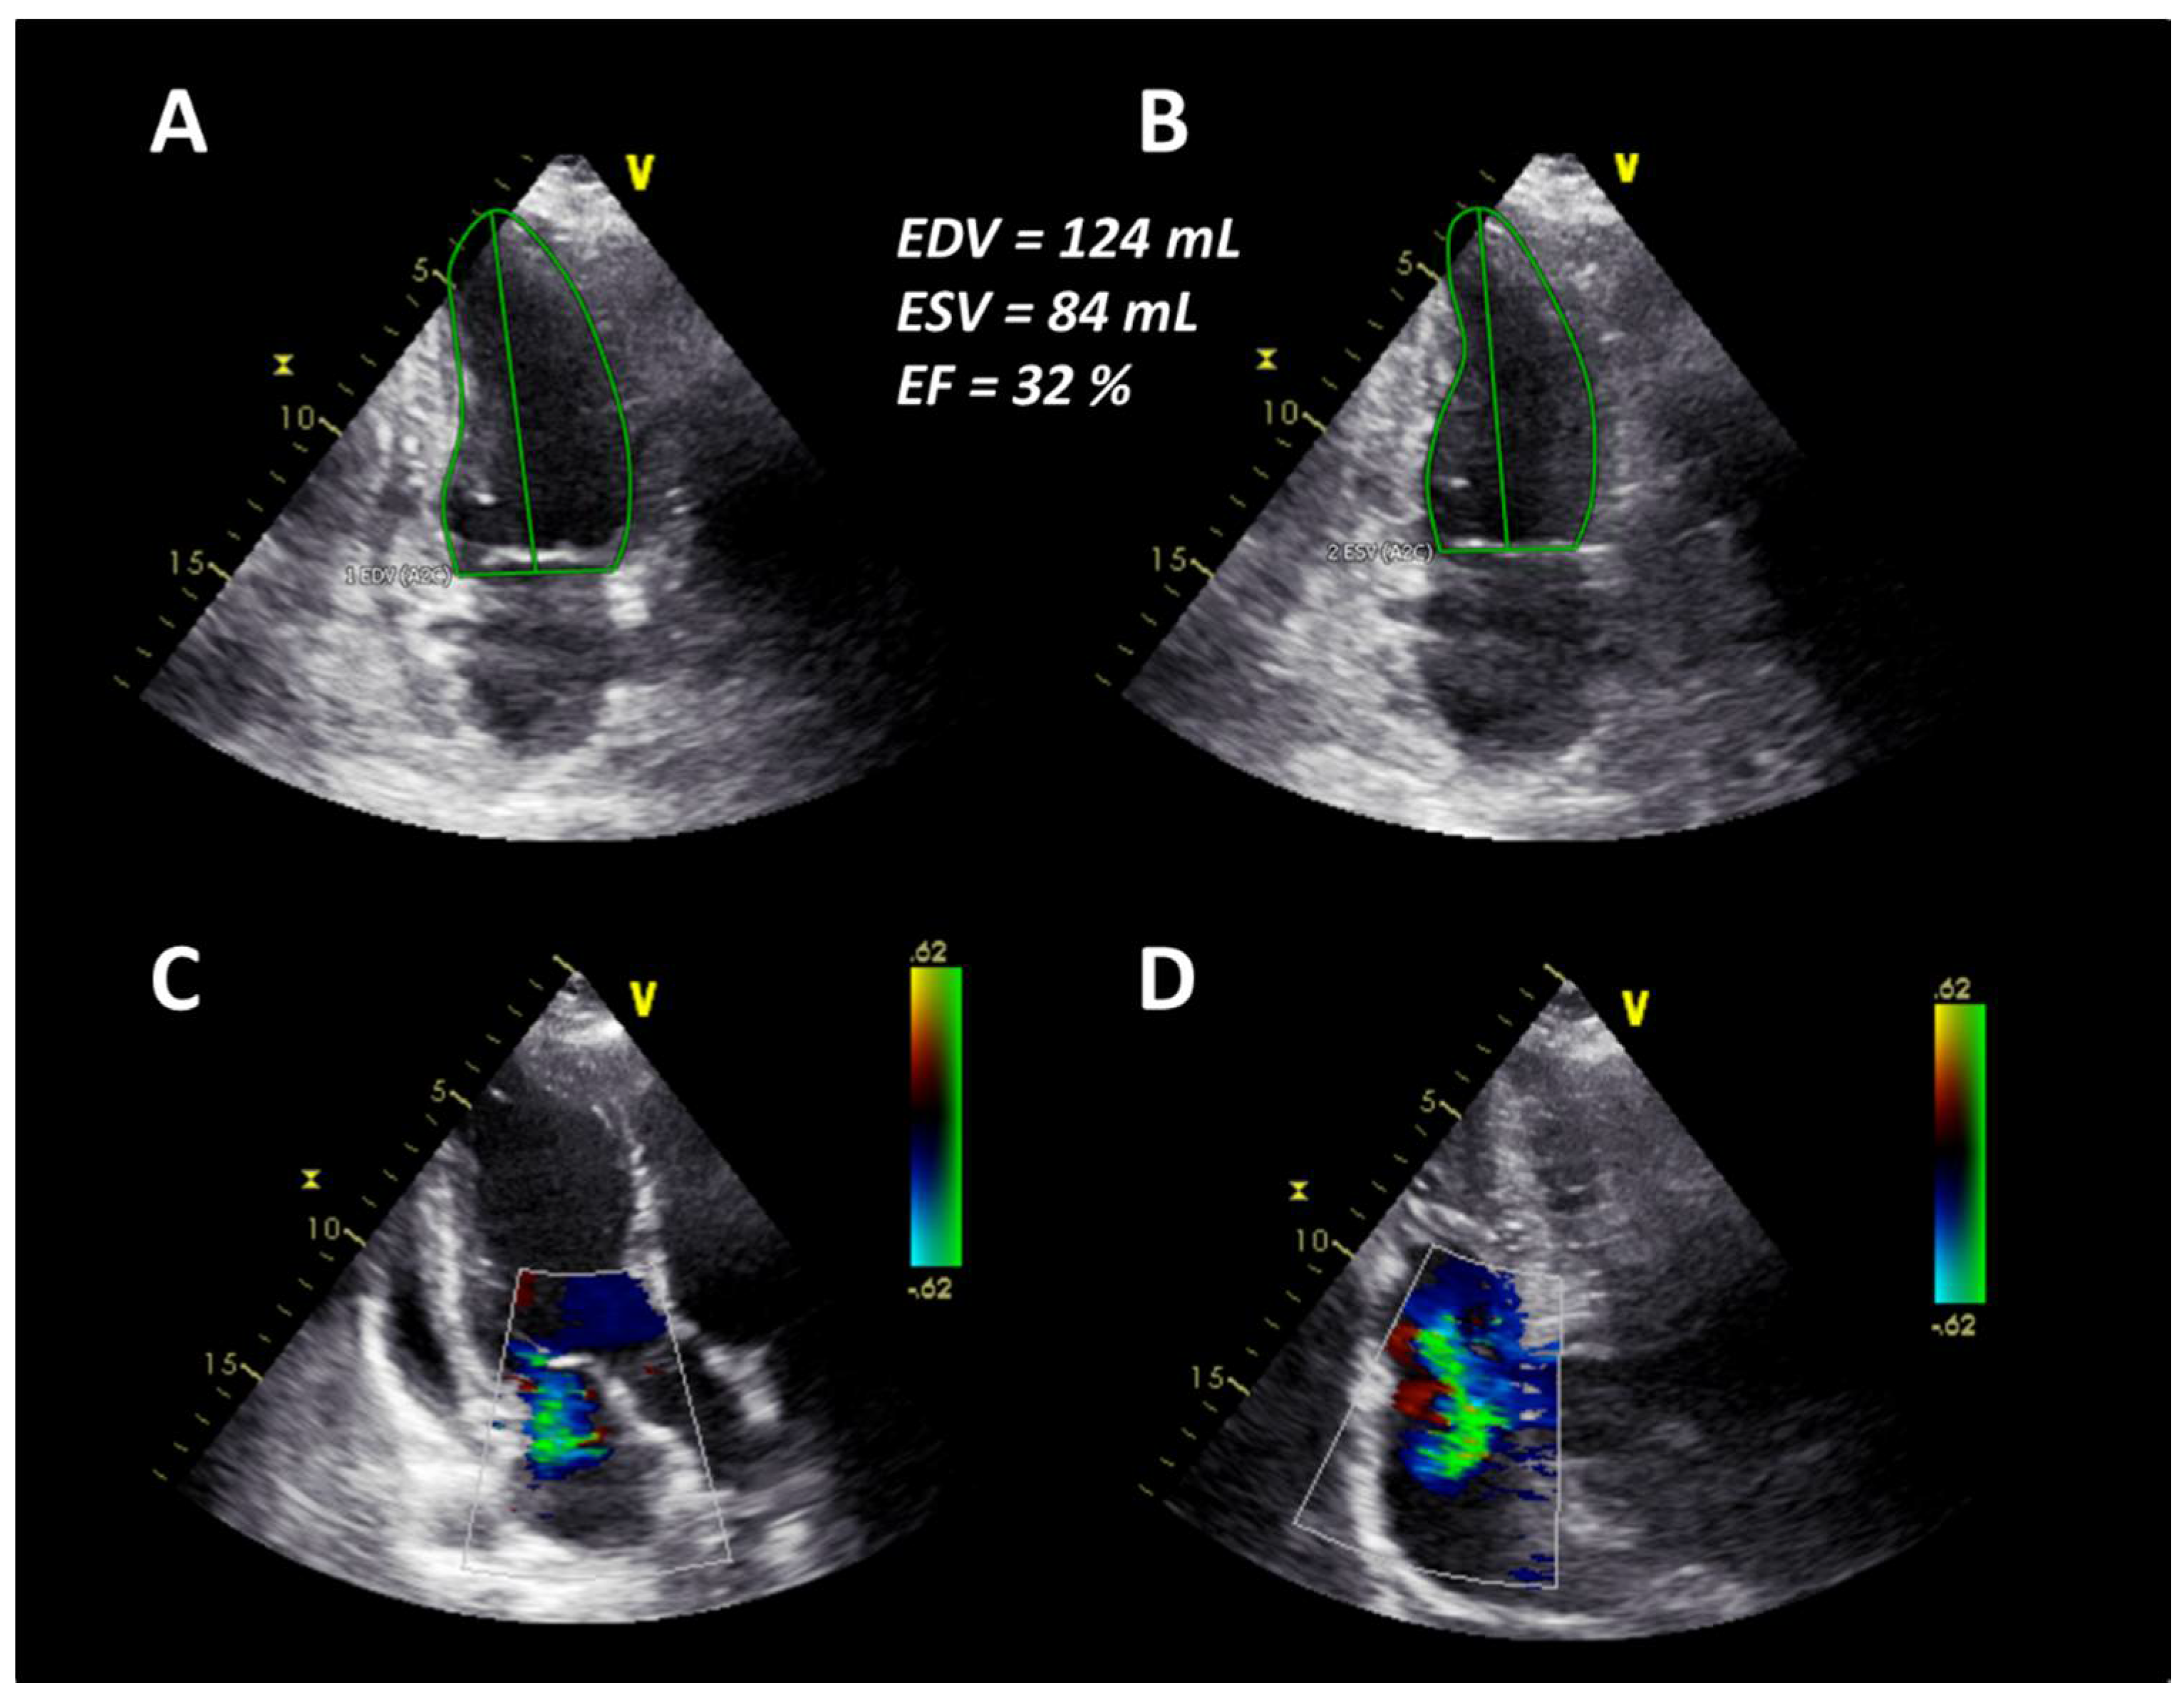

At the same time, CT changes and spirometric lung function parameters slightly improved. Subsequently, heart failure treatment was intensified with carvedilol, thiazide diuretics, and a higher dose of ACE inhibitors, resulting in concomitant improvement of cardiac parameters. Due to further progression of the disease—despite AHSCT—the patient started on monotherapy with RTX in July 2019. In August 2019, after completion of the first cycle of RTX, clinical symptoms and spirometry parameters ameliorated noticeably (FVC 72.5% predicted, FEV1 79.2% predicted, FEV1/FVC ratio 89.8%), conversely DLCO slightly deteriorated to 38.2% predicted (Figure 1). In October 2019, after completion of the second cycle of rituximab, lung function (FVC 91% predicted, FEV1 95% predicted, FEV1/FVC ratio 84%, DLCO 44% predicted) and mRSS (1 point) further improved significantly (Figure 1). There was also a significant improvement of the echocardiographic findings to a LVEF of 52%, no mitral regurgitation and mild tricuspid regurgitation (Figure 4). Additionally, NT-proBNP levels decreased to 2289 pg/mL.

In the present case, the patient initially responded to the administered immunosuppressive therapy. However, SSc relapsed and rapidly progressed resulting in the involvement of several internal organs. According to the recommendations of the EULAR [8] and a recent study by Henes et al. [9], AHSCT should be considered for the treatment of selected patients with rapid progressive SSc at high risk of organ failure. Therefore, the decision for AHSCT was made. However, only six months after AHSCT, the patient developed symptoms and systemic involvement of progressive SSc with acute heart failure again, which was unexpected as AHSCT is associated with a remission of disease activity lasting up to five years [10]. Additionally, DLCO remained low despite improvement of fibrotic changes in a HRCT scan of the lungs. Restarting RTX, however, finally led to significant improvement of the patient’s symptoms and activity score. Interestingly, heart valve regurgitations were reversible after rituximab treatment, as documented by echocardiography (Figure 4). To the best of our knowledge, this is the first report of heart valve involvement and reversible regurgitation after immunosuppression in SSc. RTX has beneficial effects in SSc patients, while there are no reported data on heart valve involvement. Furthermore, progression of SSc after such a short interval of AHSCT has not yet been reported.

Figure 4. (A) End-diastolic borders of the left ventricle in the apical two-chamber view. (B) End-systolic borders of the left ventricle in the apical two-chamber view. (C) No mitral regurgitation in the apical three-chamber view. (D) Mild tricuspid regurgitation in the apical four-chamber view.